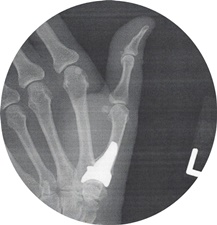

December of 2018

As for Levofloxacin damage

my wife has a Titanium Joint

implanted in her Right

Hand.